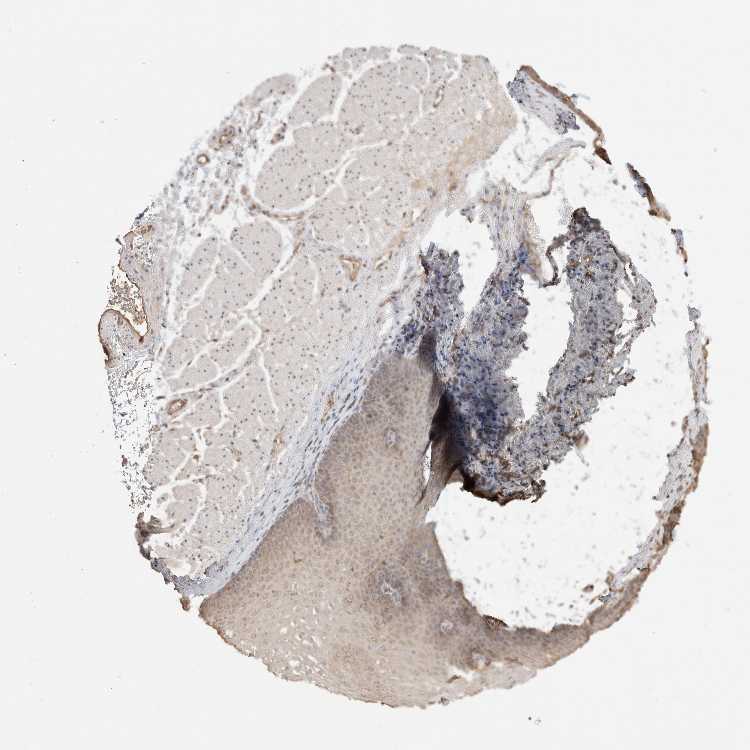

ESOPHAGUS - Antibody stainingi

Antibody staining in the annotated cell types in the current human tissue is reported as not detected, low, medium, or high, based on conventional immunohistochemistry profiling in selected tissues. This score is based on the combination of the staining intensity and fraction of stained cells.

Each image is clickable and will lead to virtual microscopy that enables deeper exploration of all samples and also displays staining intensity scores, fraction scores and subcellular localization as well as patient and tissue information for each sample.

Antibody CAB025918

Squamous epithelial cells Not detected